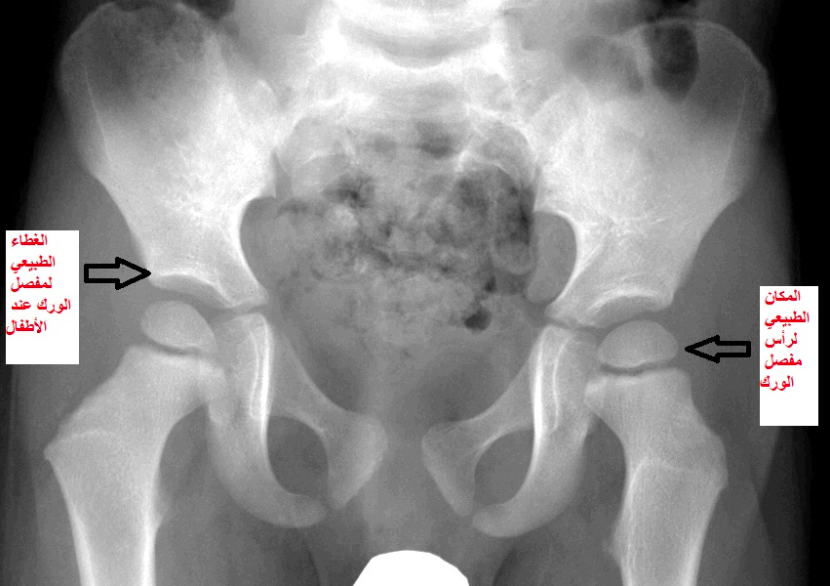

في الصورتين القادمتين تبيان لشكل مفصل الورك عند الأطفال في السنة الثانية من العمر، الأولى تبين الوضع الطبيعي لهذا المفصل الهام والثانية توضح مشكلة الخلع الولادي الكامل لمفصل الورك

الأشعة السينية الاعتيادية كالتي عرضت قبلا لأطفال في السنة الثانية من العمر لا تكون واضحة وتشخيصية لمشكلة الخلوع الولادية في الأشهر الأولى للطفل، لأن عظام الطفل في هذه السن المبكرة مازالت غير متكونة بشكل كاف يسمح بظهورها في هذا النوع البسيط من الأشعة.